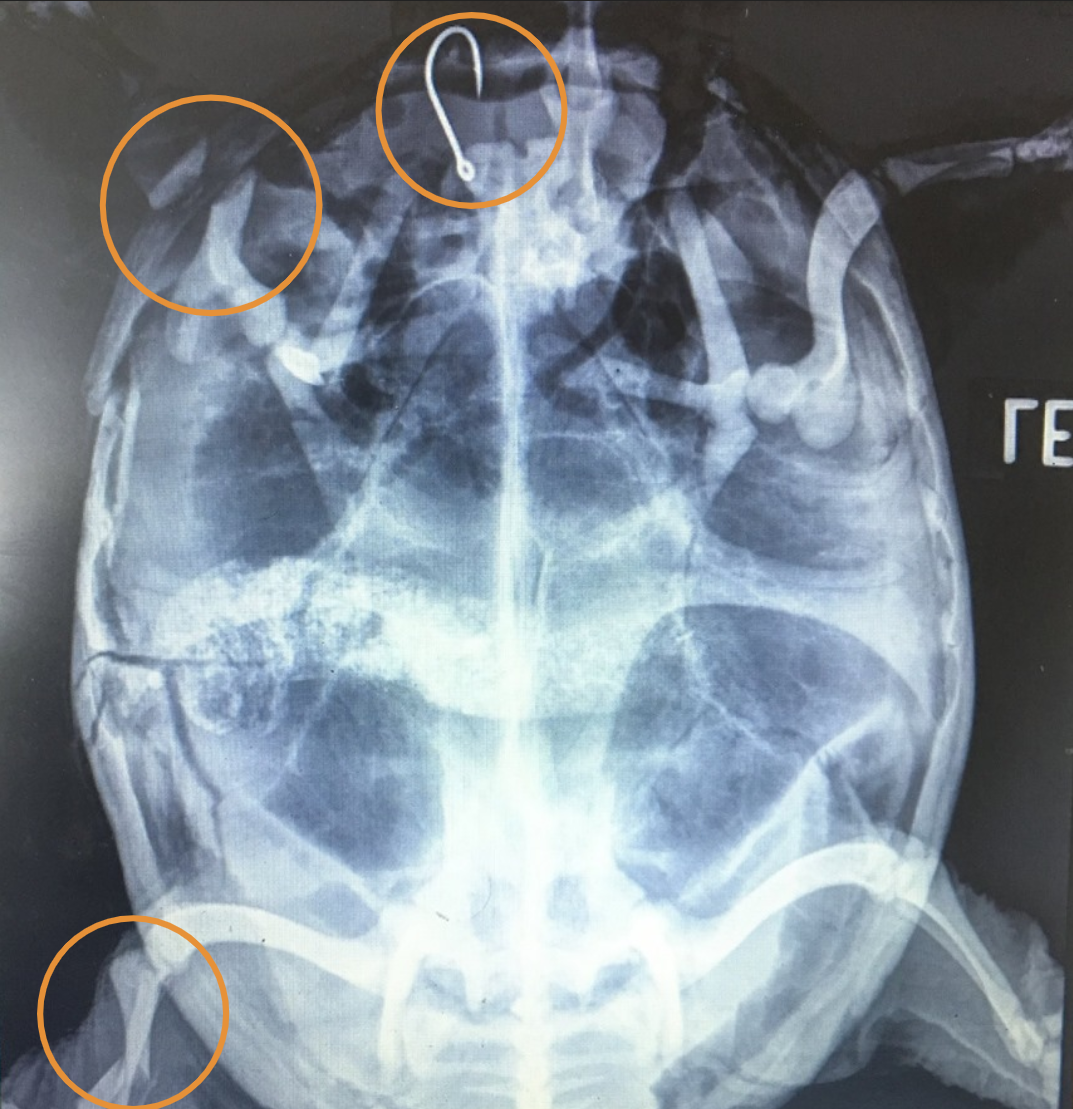

Tina Batak is a student who shared her experience as an intern at the WMC this summer. A snapping turtle with a shell fracture was brought in by a concerned community member. In her rounds presentation, Tina described to the students how she and the team handled this patient’s case throughout its time with us. She described how sedating the turtle calmed him down and let them better assess the injuries he sustained prior to coming to us. Additionally, she explained the medications used to control the pain and inflammation caused by his trauma. This is especially helpful for our first-year students who are just beginning to be exposed to these drugs and their applications. The turtle’s wounds were stabilized, and the team made plans to take radiographs (X-rays) to give them a better understanding of the extent of the patient’s injuries. Tina walked us through those radiographs, explaining the implications of the injuries.

This turtle had several severe fractures and a fishing hook embedded in his esophagus! Tina described the process of carefully removing the hook and stabilizing four of the shell fractures. Despite the team’s hard work at stabilizing the fractures, the severity of his injuries and his poor mentation meant his prognosis was guarded. Tina discussed the way this patient’s wound healing, activity level, and quality of life were evaluated every day, knowing that subtle changes in these assessments could give us subtle hints as to whether the turtle was going to pull through. Recheck radiographs can also be used to ensure bones are healing appropriately. Despite all of our efforts, unfortunately, this turtle’s injuries were too severe, and he did not make it. However, Tina was able to share her experience in monitoring this patient’s progress in the hopes that students will draw on her work when managing future cases.